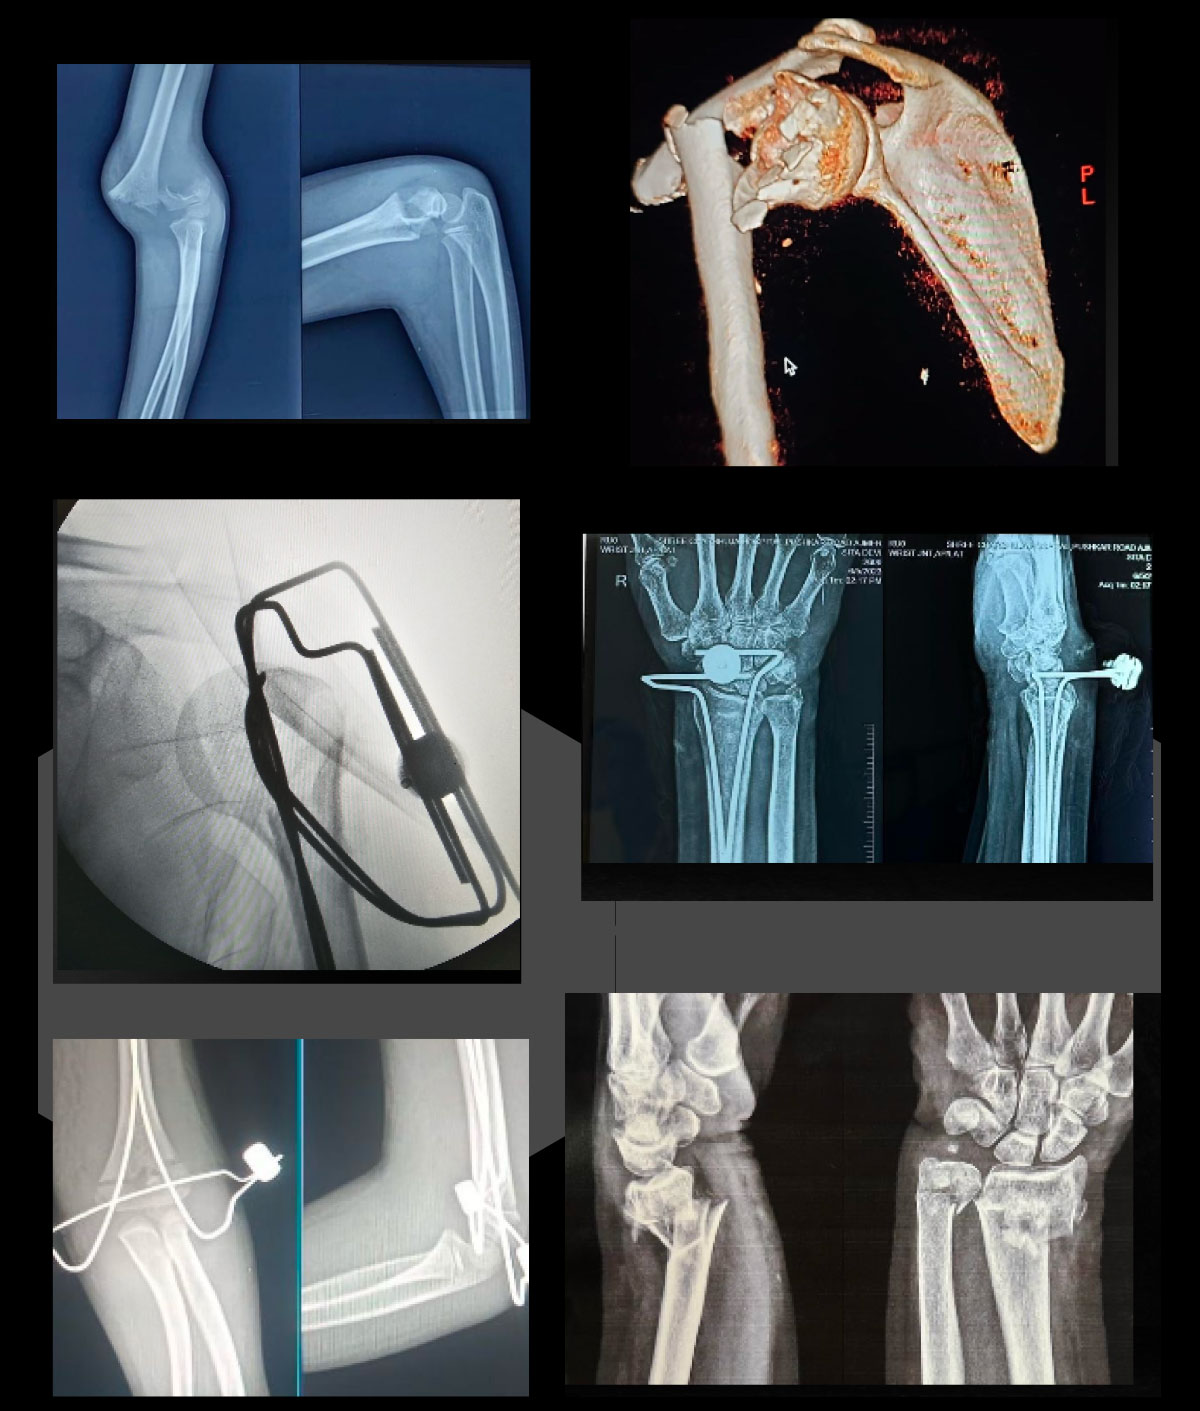

TOGETHERSPECIAL EXTRA LONG 500 MM WIRES WITH FLUTEDTIPS ONE SIDE BLUNT